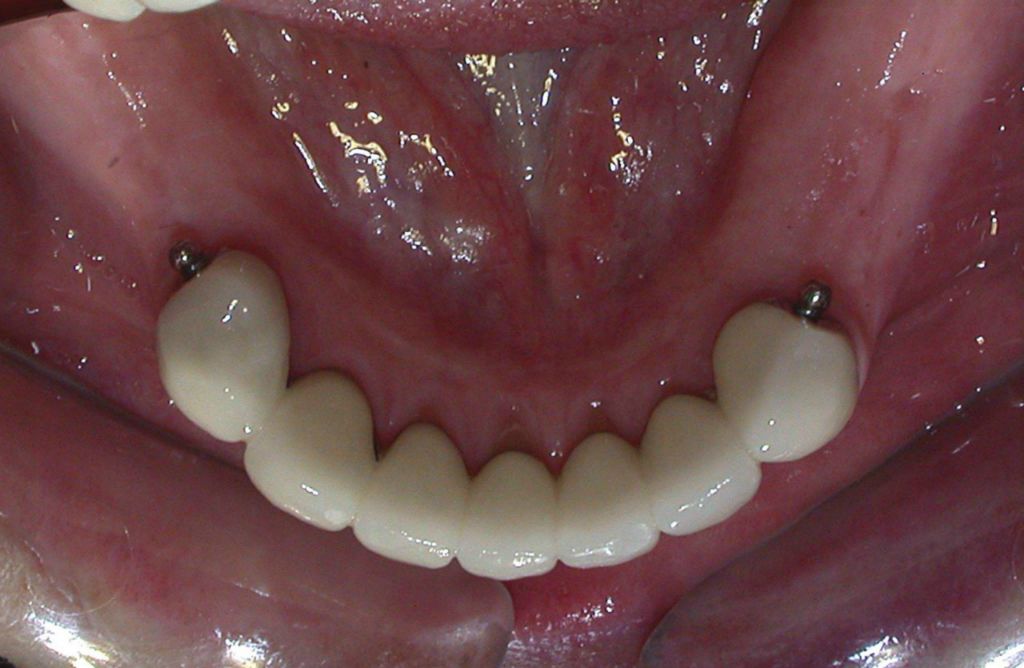

Zirconia bridge on Southern DC Implants

Tooth Replacement